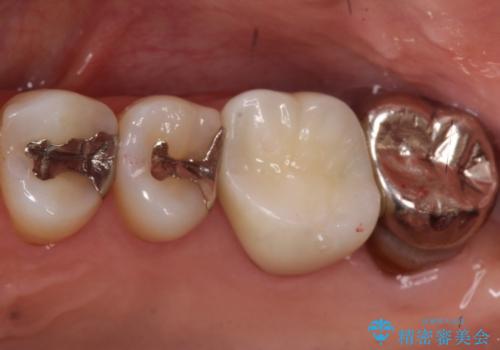

奥歯の被せ物のやり直し 精密根管治療

大きい虫歯 根管治療〜オールセラミッククラウン